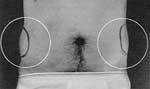

- Markings indicate the locations of fat deposits on thi spatient’s torso.

- A front view of a female patient shows abdominal and hip deposits.